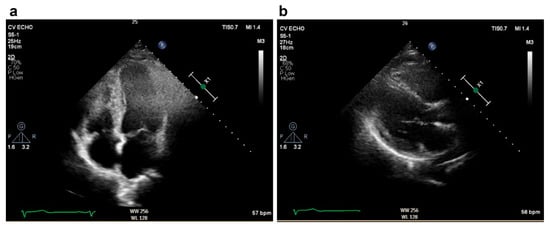

2. Case Presentation